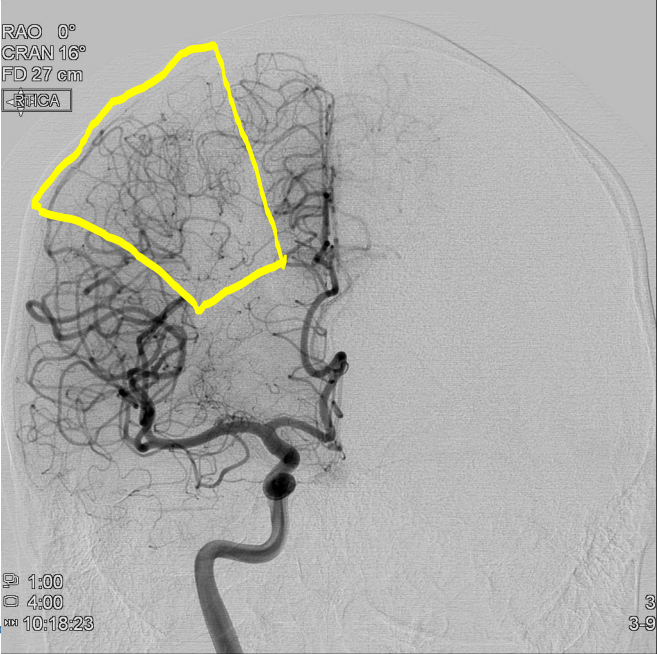

Cases 6&7 Q# 1 of 3

• 80 year old woman who presented to a partner hospital.

• 2 hours of right side weakness and trouble talking

• Exam: Afebrile, 220/120, Alert, aphasic, right face, arm, and leg hemiplegia.

• NIHSS = 22 (NIH Stroke Scale. Score of 22 = low end of **severe stroke **range)

What is the pathogenesis of her symptoms?

Cerebral ischemia

Cases 6&7 Q# 2 of 3

What vessel is the lesion in?

Left MCA (Right side weakness + hemiplegia)

**Cases 6&7 Q# 3 of 3** * 80 year old woman who presented to a partner hospital. * 2 hours of right side weakness and trouble talking * Exam: Afebrile, 220/120, Alert, aphasic, right face, arm, and leg hemiplegia. * NIHSS = 22 (NIH Stroke Scale. Score of 22 = low end of **severe stroke **range) What is the most likely cause of her stroke?

Embolism secondary to a condition like afib